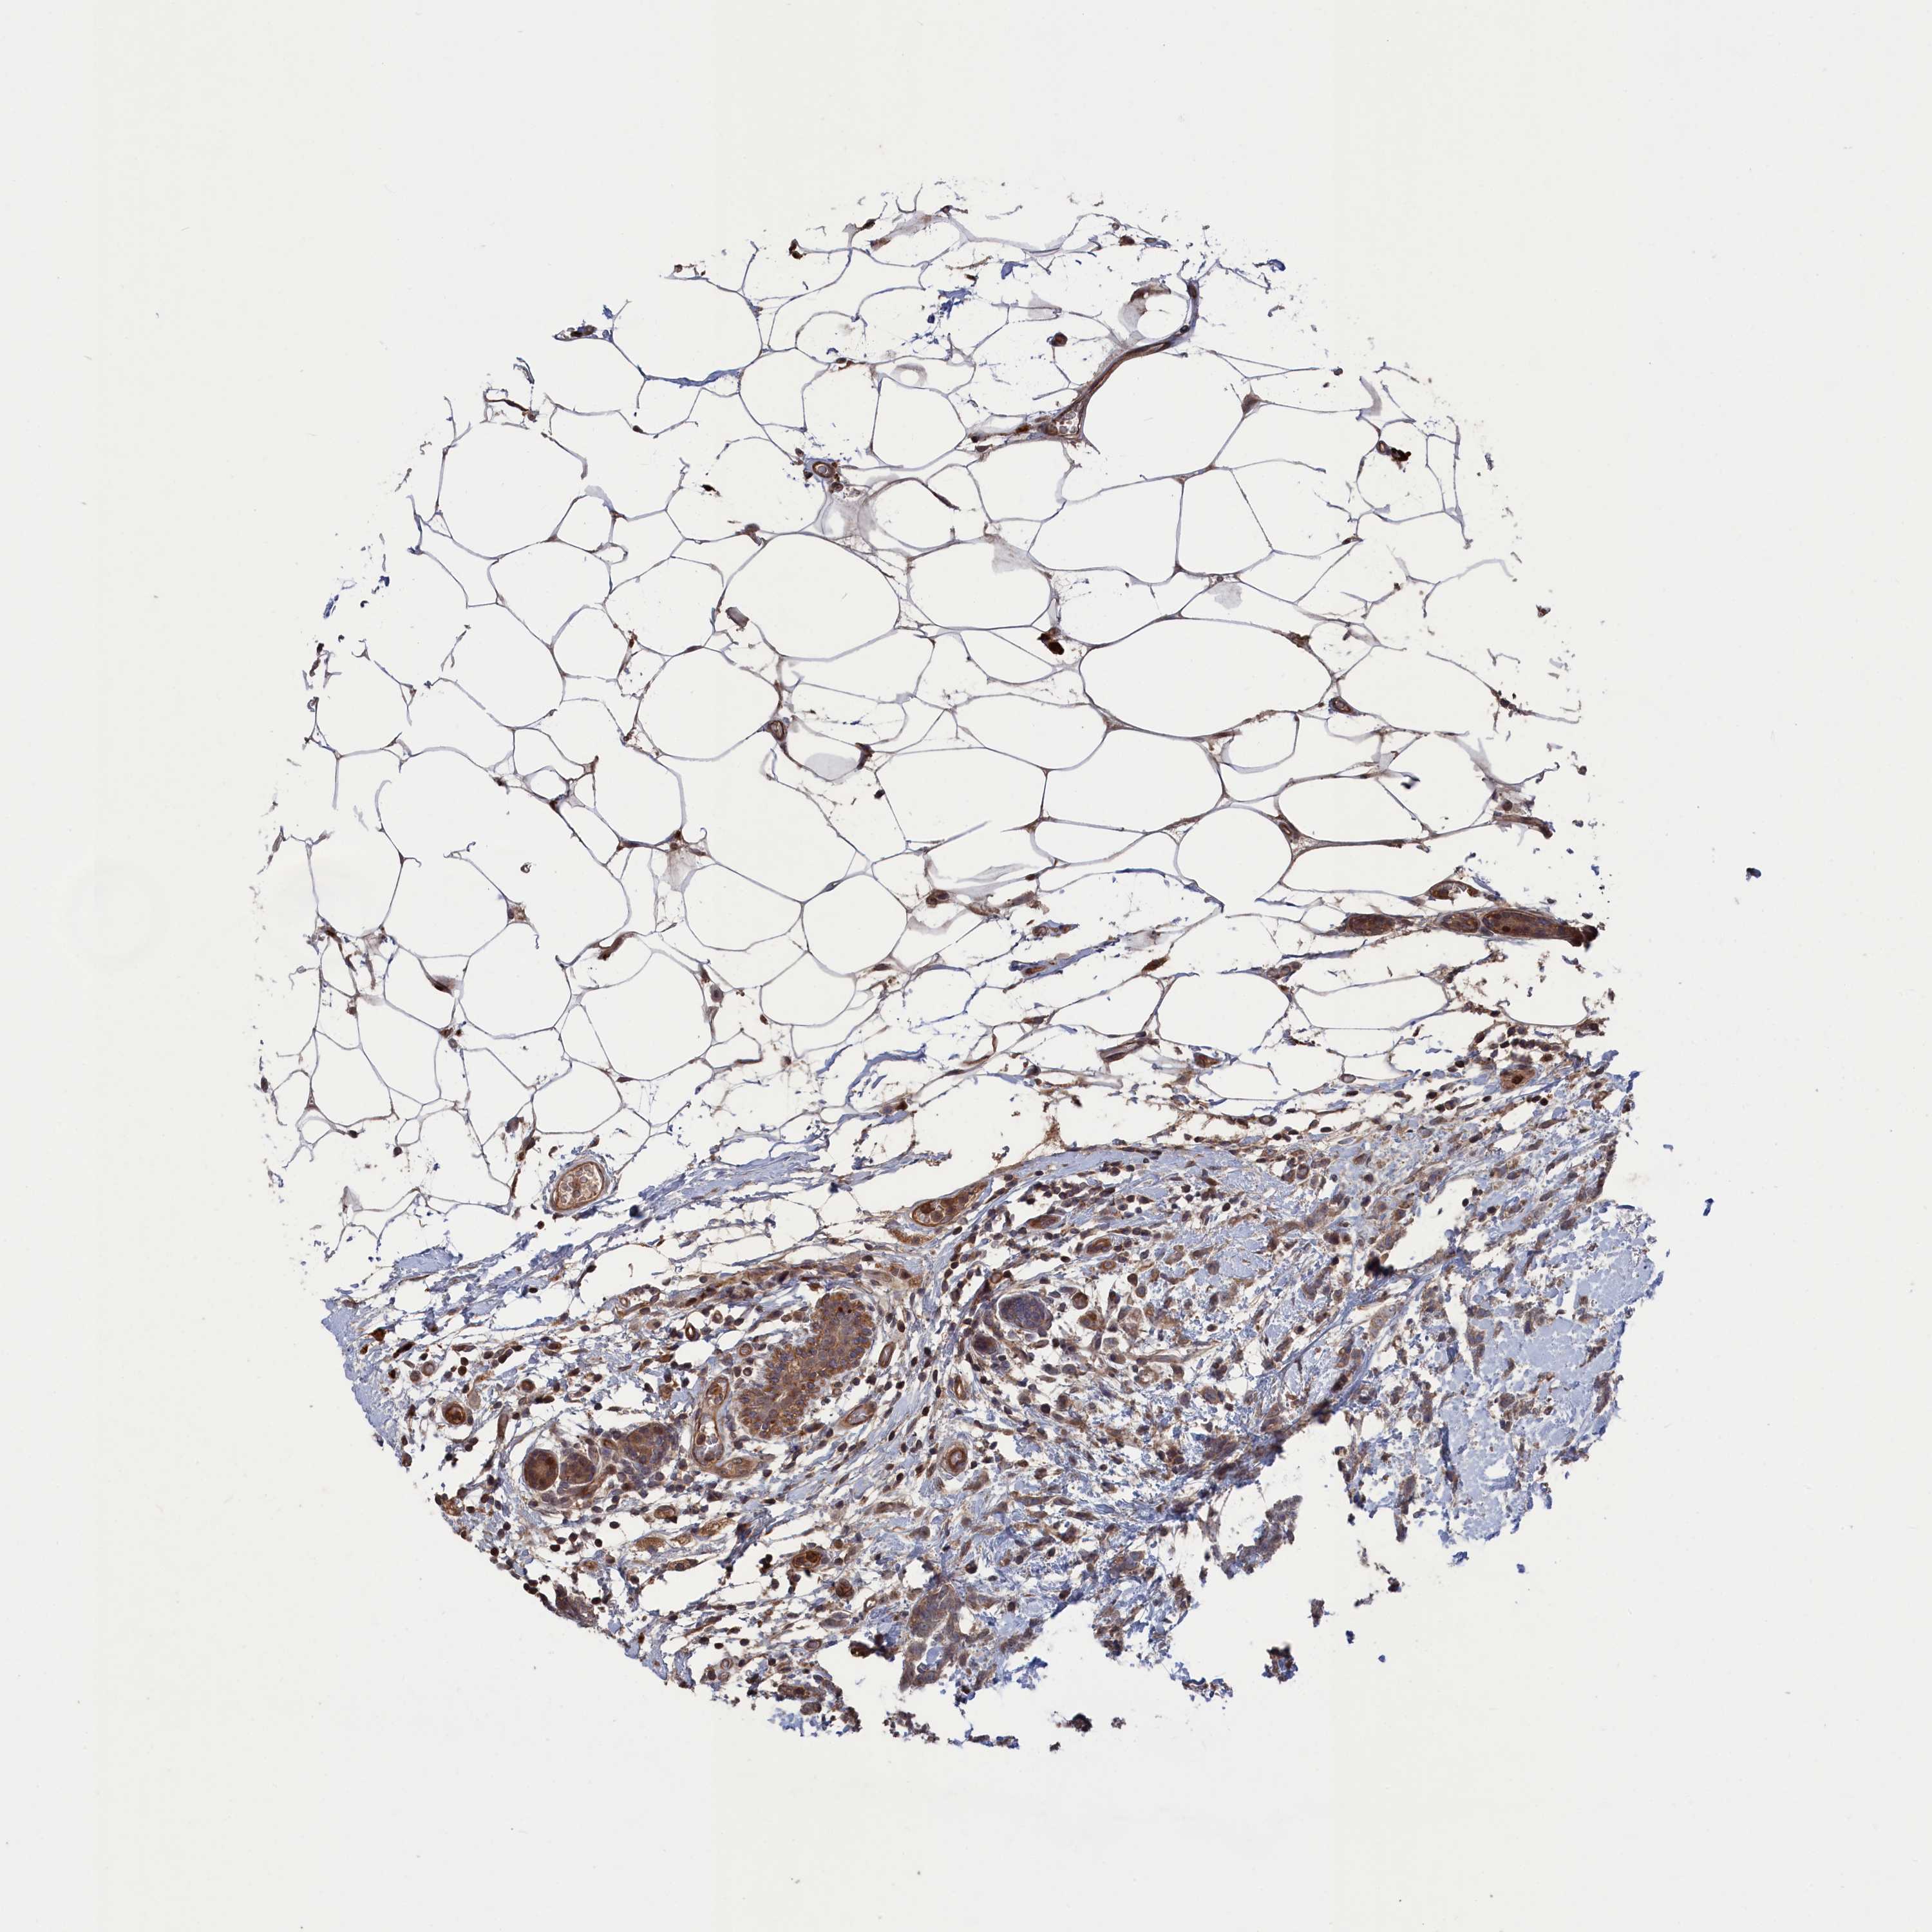

CANCER BREAST CANCER Show tissue menu

BRCA TCGA BRCA VALIDATION PROTEIN EXPRESSION